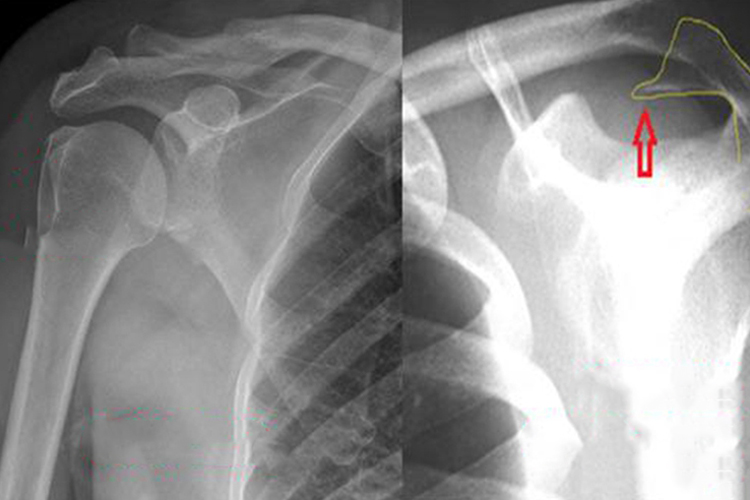

主要表现为肩膀局部关节软骨退变、关节边缘骨质增生、骨赘形成,触摸可感觉到锁骨下有骨头凸出,并伴有不同程度的关节肿痛、僵硬与不稳定,关节功能减退和畸形。影像学检查可见锁骨下有异常向下凸起的骨赘。

锁骨骨折常见于暴力损伤,如跌倒时,手掌、肘部或肩部触地,当传导暴力冲击锁骨,即可导致骨折发生。骨折内侧段因胸锁乳突肌的牵拉作用向后上移位,外侧段因上肢的重力作用和胸大肌的牵拉作用向前下方移位时,即可发现锁骨下有凸起骨头。